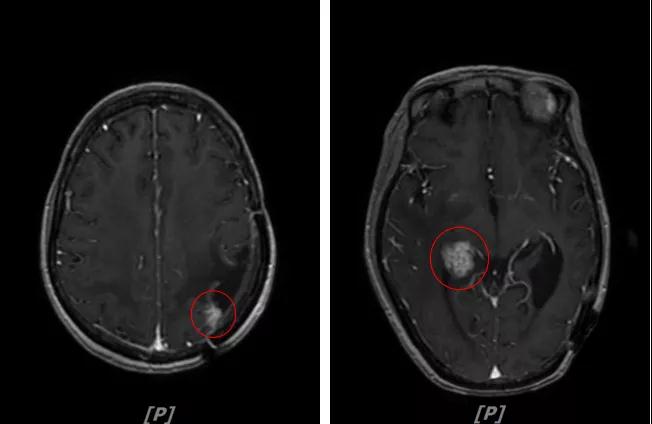

b.2014年3月全脑放疗结束后,予以LX方案治疗(拉帕替尼 1250mg qd+卡培他滨 1500mg bid)。每3个月规律复查,未见明显异常。下图为2014年6月患者行头颅增强MR检查,提示左顶叶脑转移瘤术后改变。

头颅增强MR:左侧顶枕叶见片状T1WI低信号、T2WI高信号影,增强后病灶边缘见局部斑片状强化改变,邻近脑膜轻度强化改变;右侧脑室三角区内侧见大小约8x14mm的结节影,T1WI低信号、T2WI等高信号,增强明显强化,灶周水肿明显;两侧脑室旁见片状异常信号,T1WI低信号,T2WI高信号,增强未见明显强化,余脑室、脑池、脑沟大小形态可,中线结构居中无移位

左顶叶脑转移瘤术后放疗后,左顶叶术区边缘强化灶;考虑肿瘤复发

右侧脑室三角区内侧转移瘤

两侧脑室旁云絮状异常信号,考虑放疗后改变